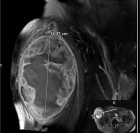

83 year old male with a two month history of a right thigh mass

Zoom image: Radiological image Radiological image.